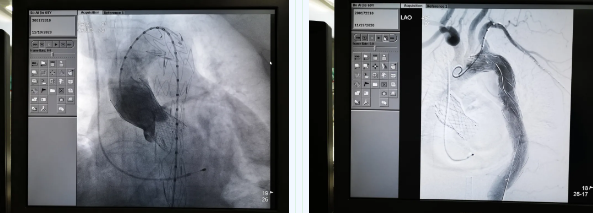

11月19日,西安國(guó)際醫(yī)學(xué)中心醫(yī)院心臟外科TAVR團(tuán)隊(duì)在心臟病醫(yī)院張金洲副院長(zhǎng)主持下,順利完成一例罕見(jiàn)“經(jīng)股經(jīng)導(dǎo)管主動(dòng)脈瓣置換術(shù) 經(jīng)導(dǎo)管主動(dòng)脈腔內(nèi)隔絕術(shù)”。經(jīng)查閱文獻(xiàn)證實(shí),此一站式復(fù)合手術(shù)國(guó)內(nèi)尚未見(jiàn)報(bào)道。由此,西安國(guó)際醫(yī)學(xué)中心醫(yī)院心外團(tuán)隊(duì)在心臟微創(chuàng)治療領(lǐng)域又向前邁進(jìn)了一大步。

張金洲副院長(zhǎng)關(guān)注著手術(shù)的每一個(gè)細(xì)節(jié),從建立軌道、跨瓣、釋放瓣膜、支架定位、造影和食道超聲確認(rèn),每一步都緊張而有序地進(jìn)行著。為了最大程度保障病人安全,心臟外科程亮副主任也帶隊(duì)建立動(dòng)靜脈入路,以備緊急體外循環(huán)。經(jīng)過(guò)團(tuán)隊(duì)每一位成員的密切配合,在近四小時(shí)的緊張奮戰(zhàn)之后,“TAVR TEVAR”復(fù)合手術(shù)順利完成;經(jīng)過(guò)造影和食道超聲證實(shí):人工主動(dòng)脈瓣無(wú)返流無(wú)瓣周漏、冠脈顯影良好,主動(dòng)脈覆膜支架無(wú)內(nèi)漏無(wú)移位。